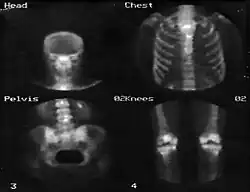

Também é possível obter uma sequência de imagens dinâmicas e sincronizá-las com outros sinais como, por exemplo, um eletrocardiograma, de forma a gerar imagens do coração durante a sístole e a diástole.[3] A figura 5 apresenta um exemplo de imagem obtida por uma câmara gama.